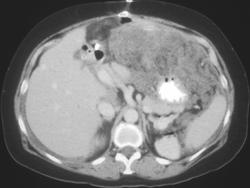

Gastric Adenocarcinoma